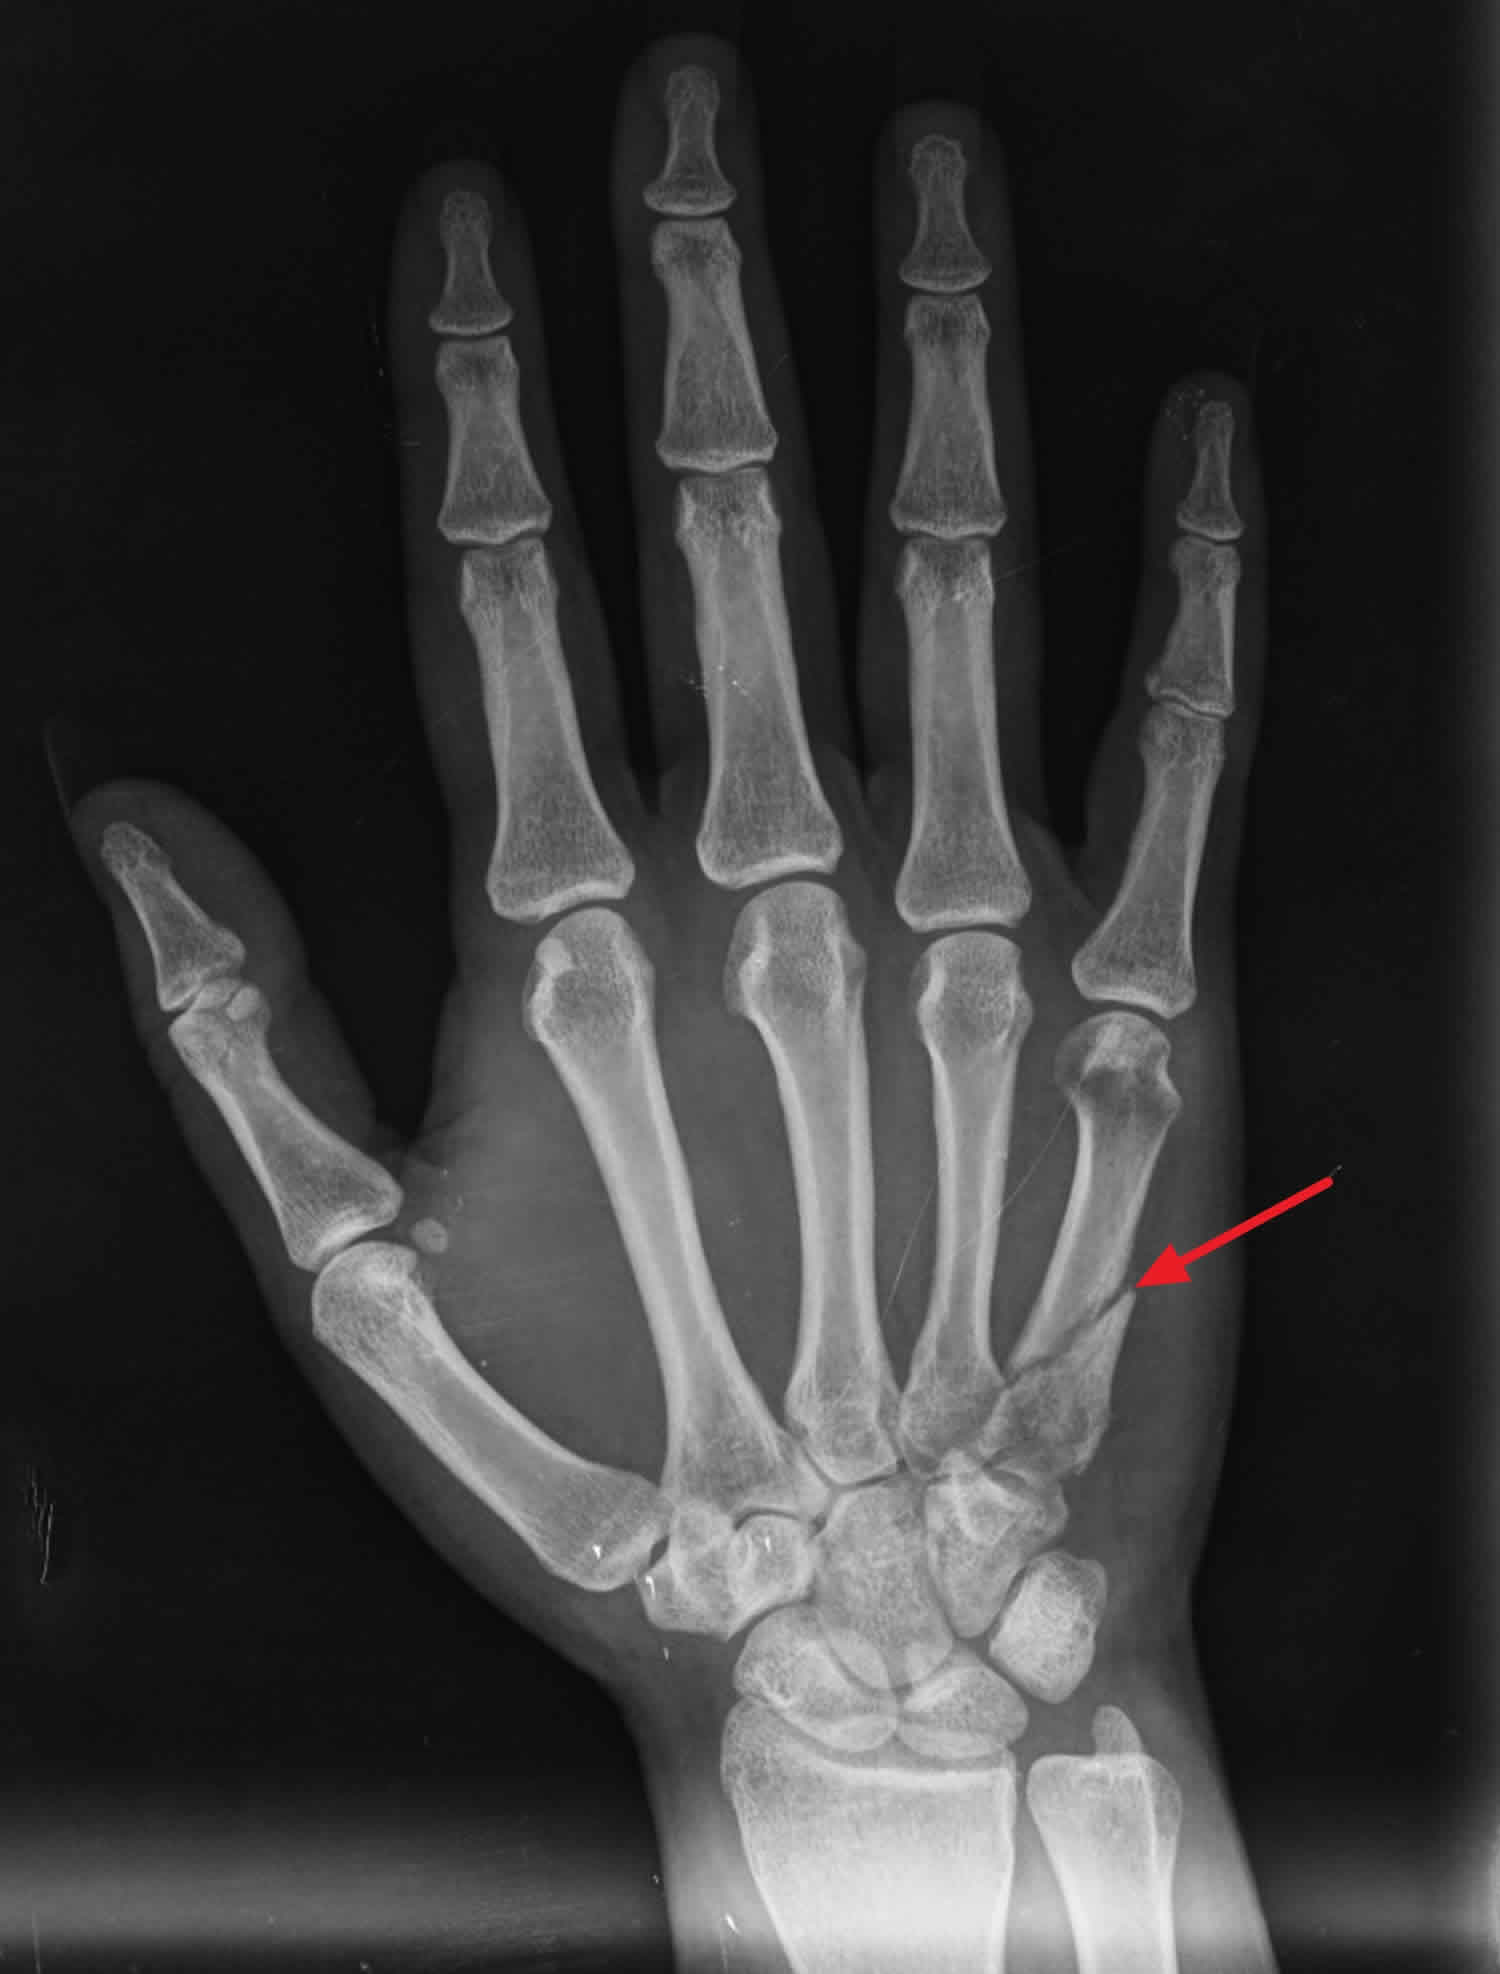

Understand the anatomy and function of the first metacarpal bone, a critical component of the human thumb. This guide covers its unique saddle joint structure, common fracture types, and clinical significance for hand mobility. Learn how this essential bone supports gripping and fine motor tasks, along with key recovery insights for injuries affecting the base of the thumb.